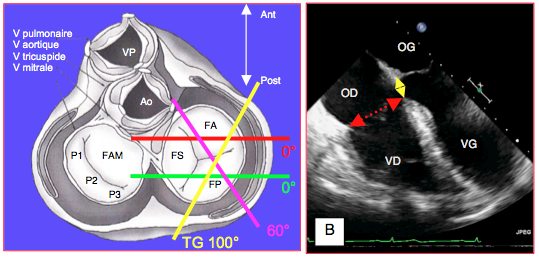

Bien que décalées, les deux valves auriculo-ventriculaires sont dans le même plan. Le plan de coupe en 4-cavités 0-20° visualise une section horizontale de la tricuspide (Figure 26.125).

Figure 26.125 : Coupes ETO de la valve tricuspide. A : Plans de coupe de la valve tricuspide (accès depuis l'oreillette, dans l’axe du coeur). En vue 4-cavités (0°), le plan de coupe passe par les feuillets antérieur (FA) et septal (FS) si la sonde est en position haute (trait rouge), mais par les feuillets postérieur (FP) et septal (FS) si la sonde est en position basse (trait vert). A 60°, on voit les feuillets antérieur et postérieur (trait bleu), comme en position transgastrique (trait jaune). Le feuillet septal n’est visible qu’en vue 4 cavités. FP : feuillet postérieur. VP: valve pulmonaire. Ao: valve aortique. B: vue 4-cavités 0° mi-œsophage; le diamètre normal (flèche rouge) est de 2.8 ± 0.5 cm. Cette image sous-estime la surface anatomique réelle de l'anneau tricuspidien car celui-ci est ovale, et cette vue en mesure le plus petit diamètre. La flèche jaune représente le décalage apical d'envion 10 mm entre l'insertion septale de la valve tricuspide et celle de la mitrale.